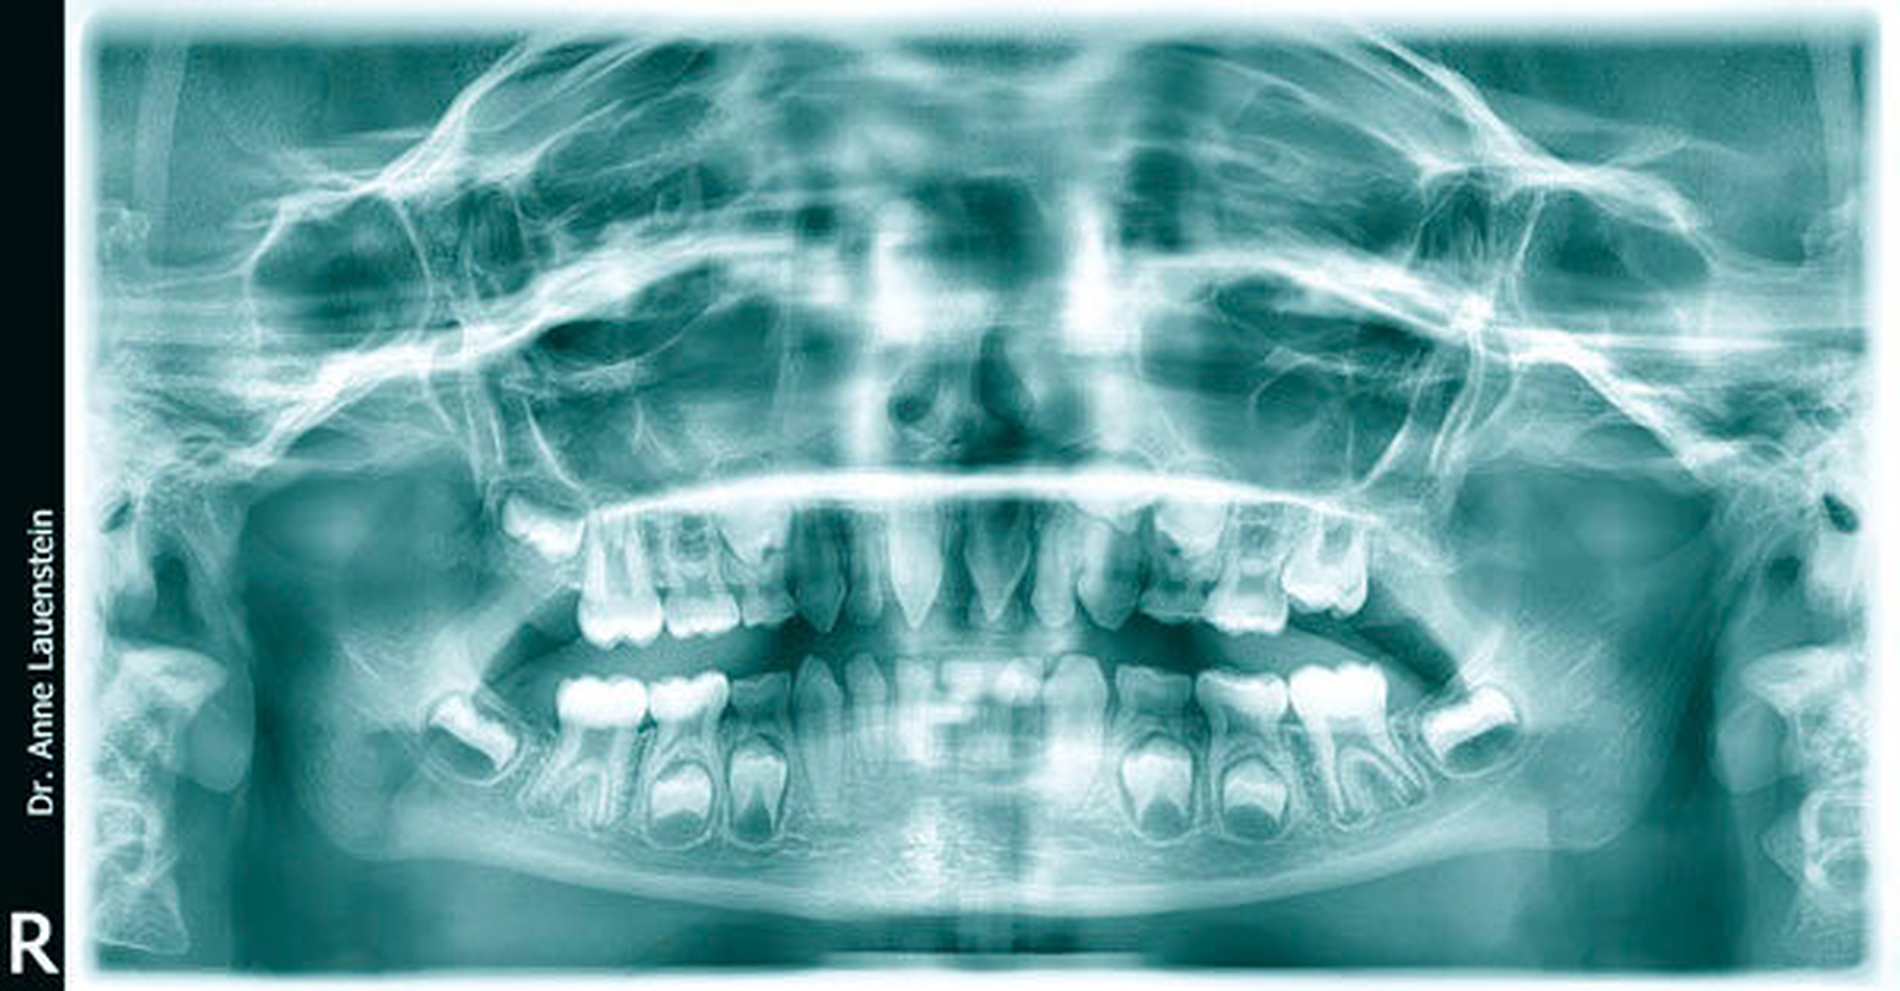

Sodann wurde ein OPG angefertigt. Auf dem Röntgenbild waren Zahnanlagen für die Permanentes 14, 23, 24, 35, 34, 44 und 45 erkennbar (Abbildung 3). Die Zähne zeigten – bis auf den Milchzahn 61 – keinen Lockerungsgrad.